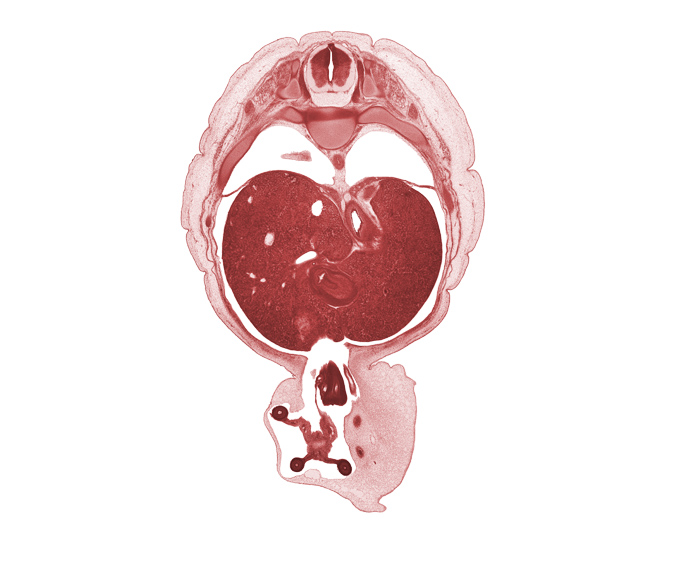

Carnegie Embryo #4090 | Location: 20-7

Keywords: T-9 intercostal nerve, T-9 spinal ganglion, appendix, caudate lobe of liver, central canal, cephalic edge of suprarenal gland cortex, distal limb of herniated midgut, duodenum (first part), iliocostalis muscle, junction of esophagus and stomach, junction of peritoneal cavity and umbilical coelom, longissimus muscle, lung, right, proximal limb of herniated midgut, rib 10, spinalis muscle, umbilical vesicle stalk, wall of pyloric antrum of stomach

Source: The Virtual Human Embryo.